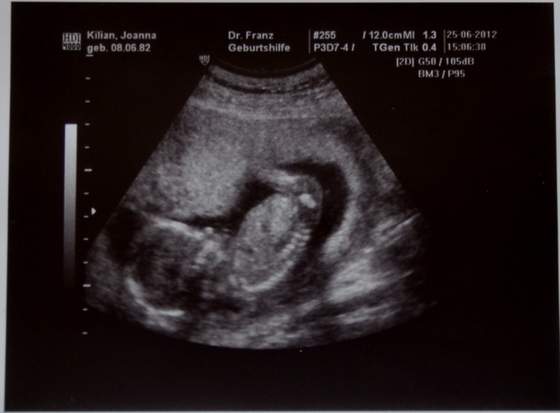

a dzidzia widze ładnie rośnie moja w 13tc miała 6,75mm a Twoja widze długa :-)